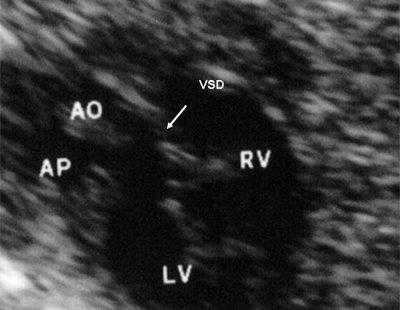

В равной степени это относится к дефекту межжелудочковой перегородки (рис. 6), простой форме транспозиции магистральных сосудов (рис. 7, 8), транспозиции магистральных сосудов с дефектом межжелудочковой перегородки (синдром Тауссиг - Бинга) (рис. 9), общему желудочку (рис. 10), общему артериальному стволу (рис. 10), двойному отхождению сосудов от одного из желудочков сердца (рис. 11).

Рис. 6. Дефект межжелудочковой перегородки. Длинная ось сердца. Стрелками показан дефект межжелудочковой перегородки.

Рис. 9. Синдром Тауссиг - Бинга. Легочная артерия (отмечена стрелкой) расположена над дефектом межжелудочковой перегородки.

LV и RV - левый и правый желудочек, АР - легочная артерия, АО - аорта, VSD - дефект межжелудочковой перегородки.